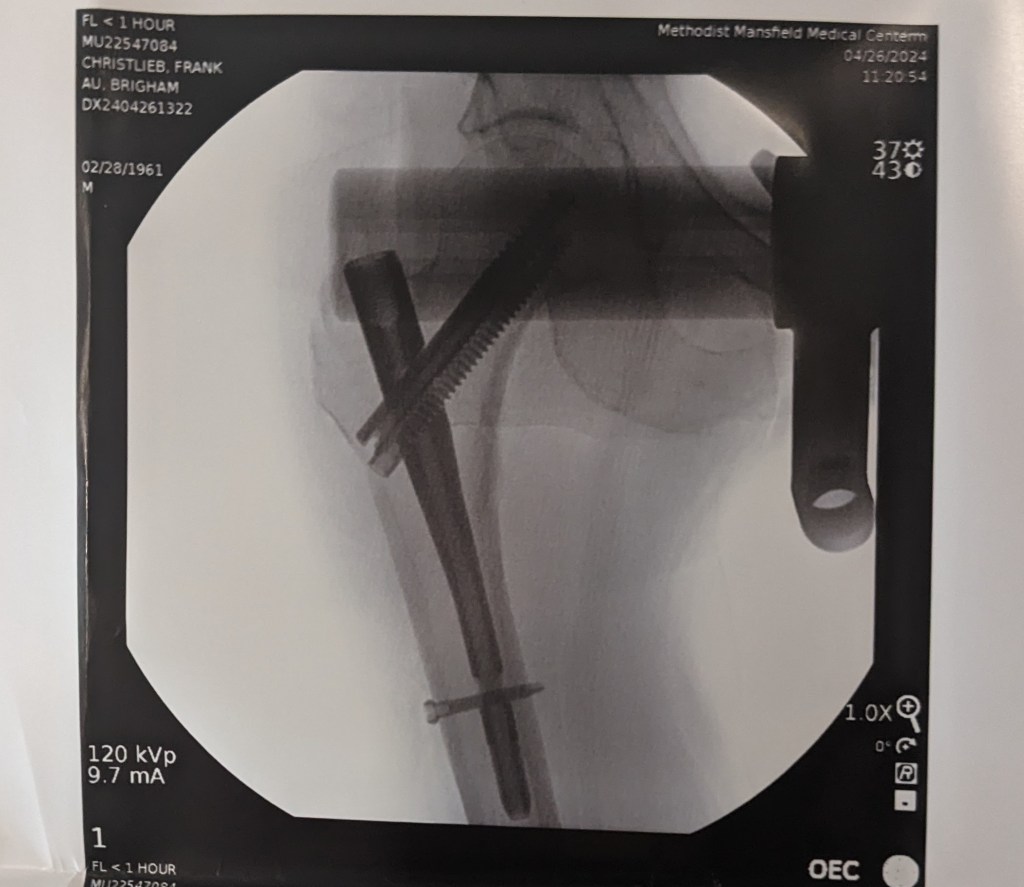

In the middle of the night, I fell and broke my right femur (thigh bone) just below the ball-and-socket hip joint. Just after 11 a.m. Friday, I had surgery to have a rod and screws inserted to repair it. Now my body will have to do its own repairs.

I was scheduled for surgery at 1 p.m., then moved up to 11ish, and we met Dr. Brigham Au, the surgeon who’d be operating on me. It was he who told us I didn’t have a broken hip but a broken femur — an intertrochantery femur fracture, to be technically precise.

This image shows the rod and screws Dr. Brigham Au put in my right femur. You really can’t see the break, but it starts at upper left and runs down under the ball and socket hip joint.